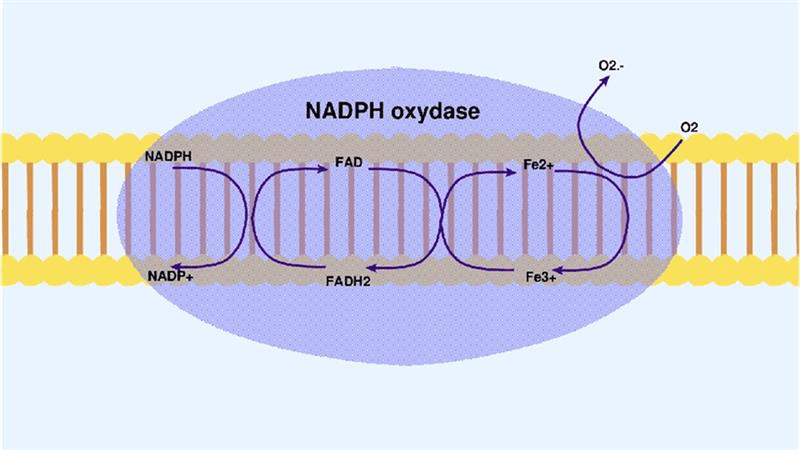

Therapeutic Targets Associated with Medical Research in the Treatment of Inflammatory Bowel Disease

Inflammatory bowel disease (IBD) is a multifactorial disease of the digestive tract. Their prevalence has increased considerably over the previous...Read More